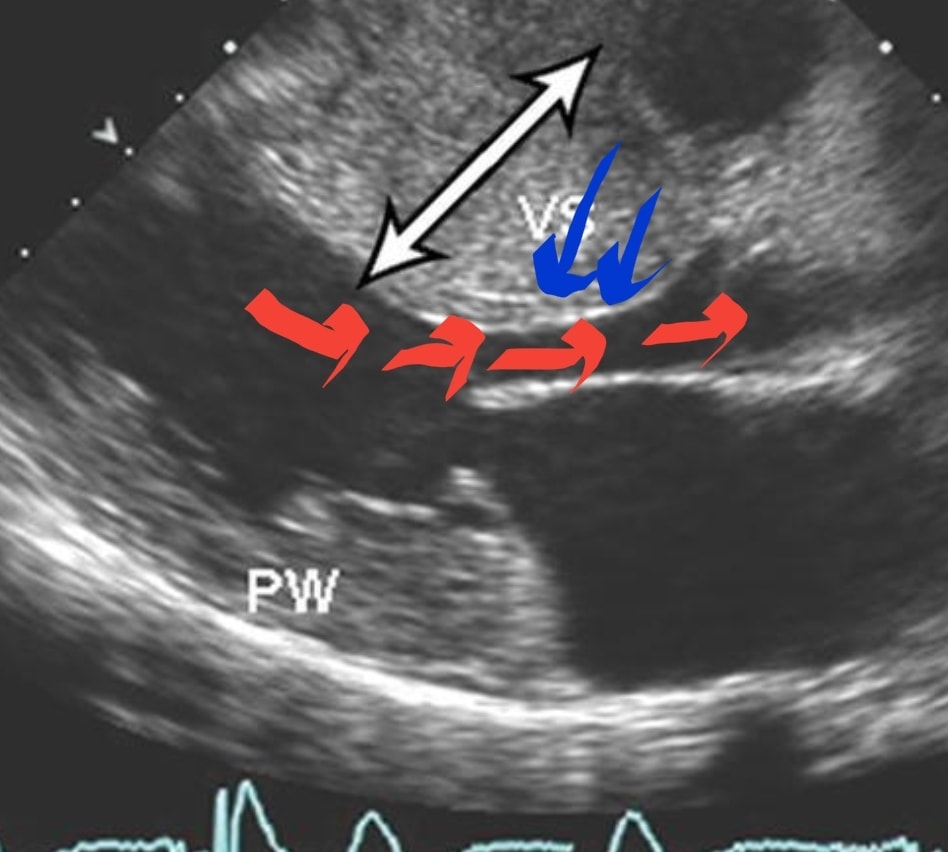

Гипокинезия лж

Гипокинезия лж 55 фотографий